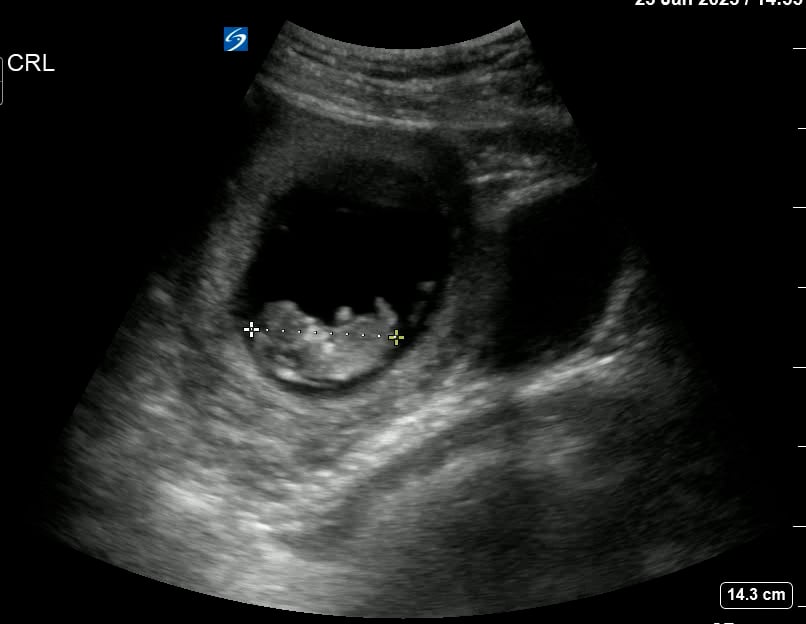

In OBGYN, the gestational sac is the first sonographic sign of an intrauterine pregnancy, appearing as a small, fluid-filled structure within the uterus. It typically becomes visible via transvaginal ultrasound around 4.5 to 5 weeks of gestation. This sac encloses the developing embryo and yolk sac, providing essential early nourishment and protection. Identifying the gestational sac is crucial for confirming pregnancy, assessing its location, and estimating gestational age.

Its presence on ultrasound confirms an early viable pregnancy within the uterine cavity, helping clinicians differentiate it from ectopic pregnancies. Monitoring the gestational sac’s size and growth is vital for early pregnancy assessment, aiding in the diagnosis of potential complications. This makes the gestational sac a cornerstone for early medical and ultrasound evaluations in obstetrics and gynecology.